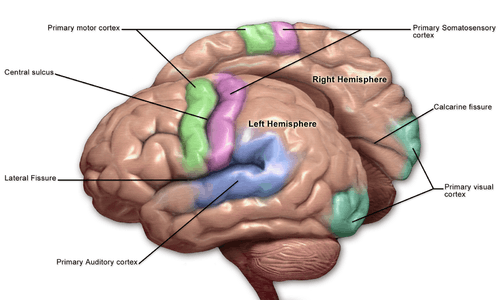

Brodmann areas 3, 1, and 2 make up the primary somatosensory cortex of the human brain (or S1). Because Brodmann sliced the brain somewhat obliquely, he encountered area 1 first; however, from anterior to posterior, the Brodmann designations are 3, 1, and 2, respectively.

Brodmann area (BA) 3 is subdivided into areas 3a and 3b. Where BA 1 occupies the apex of the postcentral gyrus, the rostral border of BA 3a is in the nadir of the Central sulcus, and is caudally followed by BA 3b, then BA 1, with BA 2 following and ending in the nadir of the postcentral sulcus. BA 3b is now conceived as the primary somatosensory cortex because 1) it receives dense inputs from the NP nucleus of the thalamus; 2) its neurons are highly responsive to somatosensory stimuli, but not other stimuli; 3) lesions here impair somatic sensation; and 4) electrical stimulation evokes somatic sensory experience. BA 3a also receives dense input from the thalamus; however, this area is concerned with proprioception.

Areas 1 and 2 receive dense inputs from BA 3b. The projection from 3b to 1 primarily relays texture information; the projection to area 2 emphasizes size and shape. Lesions confined to these areas produce predictable dysfunction in texture, size, and shape discrimination.

Somatosensory cortex, like other neocortex, is layered. Like other sensory cortex (i.e., visual and auditory) the thalamic inputs project into layer IV, which in turn project into other layers. As in other sensory cortices, S1 neurons are grouped together with similar inputs and responses into vertical columns that extend across cortical layers (e.g., As shown by Vernon Mountcastle, into alternating layers of slowly adapting and rapidly adapting neurons; or spatial segmentation of the vibrissae on mouse/rat cerebral cortex).

This area of cortex, as shown by Wilder Penfield and others, is organized somatotopically, having the pattern of a homunculus. That is, the legs and trunk fold over the midline; the arms and hands are along the middle of the area shown here; and the face is near the bottom of the figure. While it is not well-shown here, the lips and hands are enlarged on a proper homunculus, since a larger number of neurons in the cerebral cortex are devoted to processing information from these areas.

The positions of Brodmann areas 3, 1, and 2 are - from the nadir of the central sulcus toward the apex of the postcentral gyrus - 3a, 3b, 1, and 2, respectively.